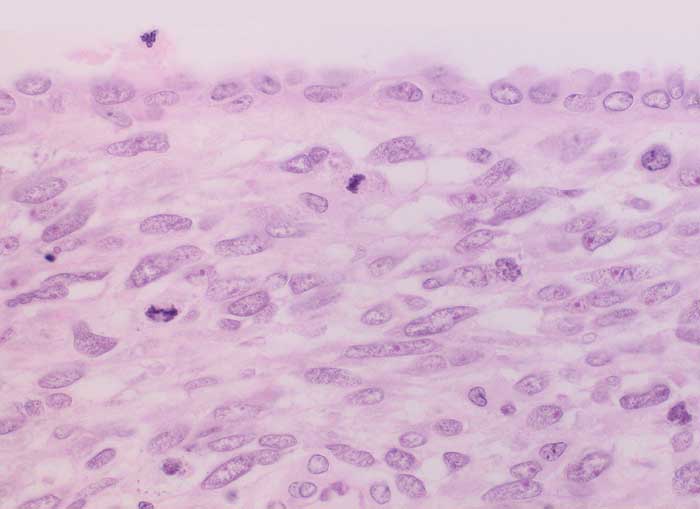

Adenosarkom

maligner Tumor

Uterus

Genitalorgane, weiblich

Postmenopausale Blutungsstörung, sonographisch suspekter Endometriumbefund, klinisch V.a. Endometriumkarzinom.

Histologie

400